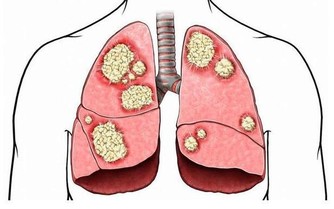

大腸癌也會導致慢性腹瀉,但可能不全是腹瀉,也可能表現為腹瀉和便秘反復交替發生。